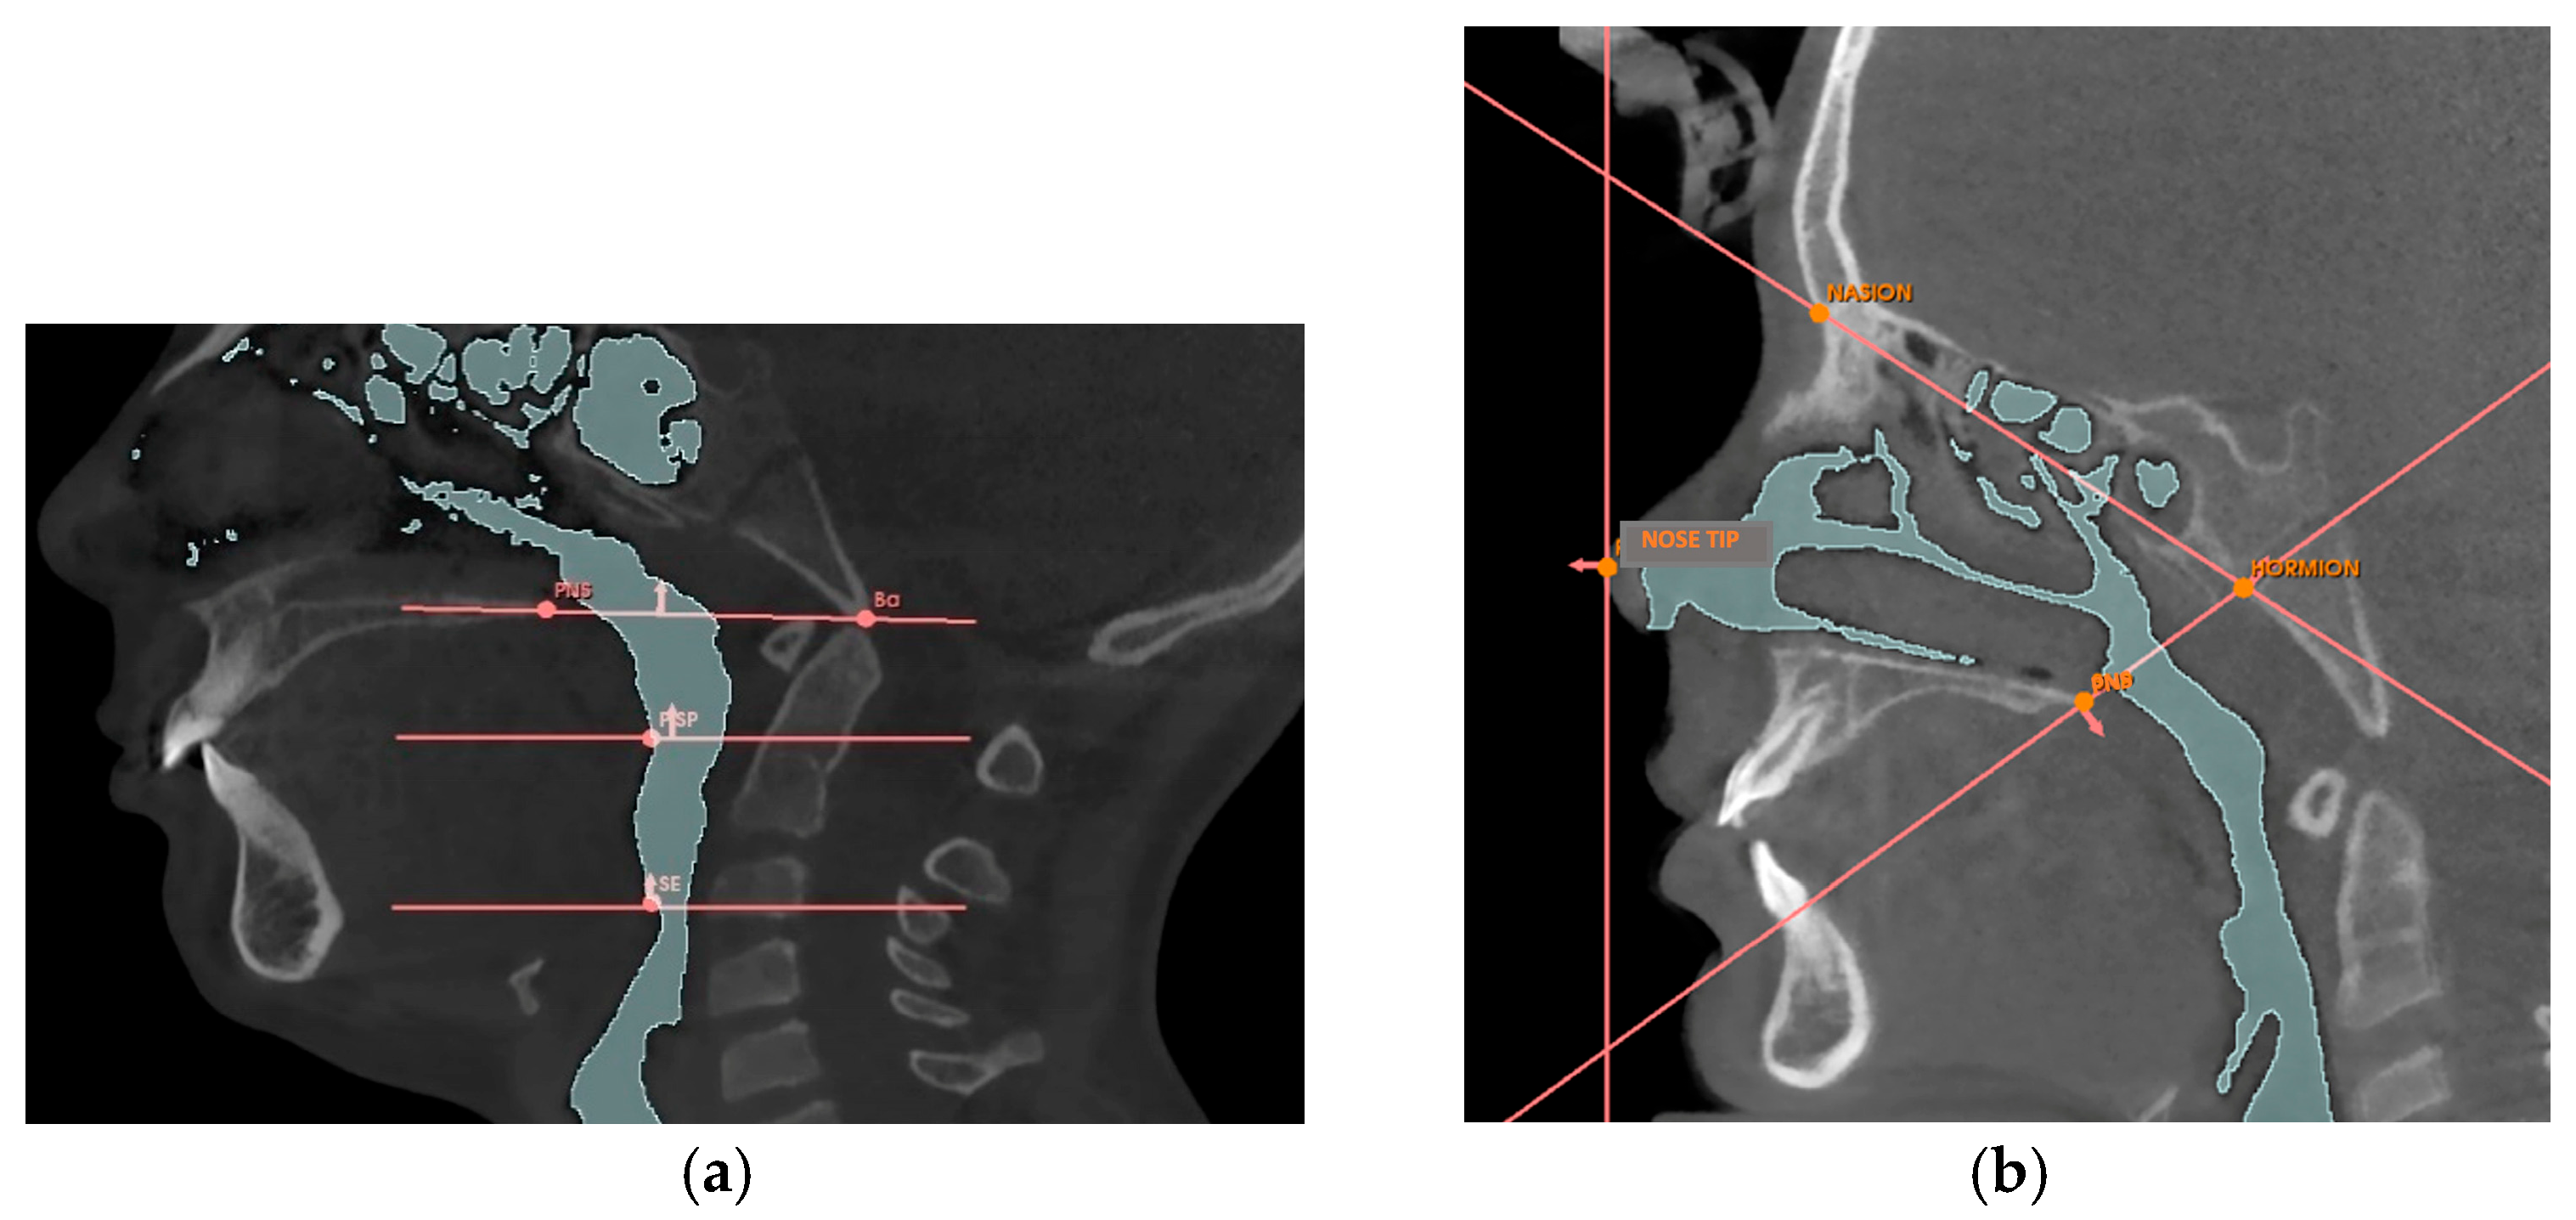

Appendix A.2. Volumetric Measurement Protocol

| Reference Point | Description |

|---|---|

| Nose tip | The most anterior point of the nose |

| PNS | Posterior nasal spine, the most posterior point of the hard palate |

| Hormion [42] | Point where the posterior border of the vomer articulates with the sphenoid bone |

| Nasion | The most anterior point of the fronto-nasal suture |

| BA | Basion, the lowest point of the anterior border of the foramen magnum |

| PISP | Posteroinferior point of the soft palate, the most posterior and inferior point of the soft palate |

| SE | Superior point of the epiglottis, the uppermost point of the epiglottis |

| Planes | Description |

| Nasal Perpendicular | Vertical plane passing through the tip of the nose |

| Hormion-PNS | Plane passing through the Hormion point and the PNS point |

| Hormion-Nasion | Plane passing through the Hormion point and the Nasion point |

| Ba-SPN [43] | Plane passing through the Ba point and the PNS point |

| Soft palate plane [43] | Horizontal plane passing through the PISP point |

| Epiglottis plane [43] | Horizontal plane passing through the SE point |